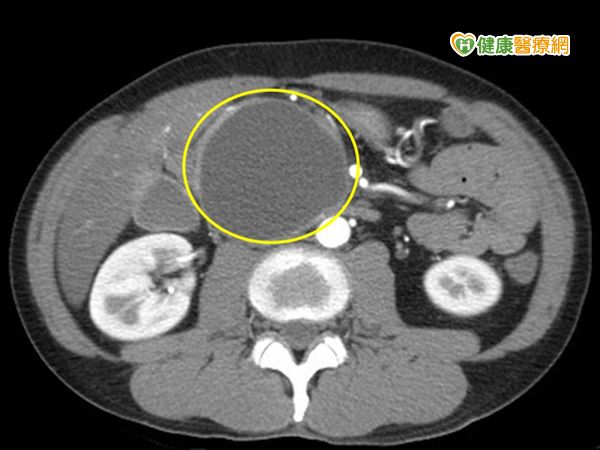

(健康醫療網/記者郭庚儒報導)45歲的黃先生長期酗酒,時常感覺腹脹,吃一點東西就脹氣,3個月內暴瘦10多公斤,曾因急性胰臟炎就醫;日前又因肚子劇痛就醫,檢查竟發現罹患急性胰臟炎,且胰臟假性囊腫長達6公分,裡面都是膿瘡。

收治個案的台北慈濟醫院胃腸肝膽科主治醫師陳建華指出,胰臟假性囊腫是由壞死細胞、水分或其他胰臟代謝物形成的大膿瘡,患者的囊腫已壓迫到十二指腸,才會造成食慾不振,觀察6周發現囊腫未自行吸收消失,建議進一步接受治療,以免嚴重感染造成敗血症,恐危及性命。